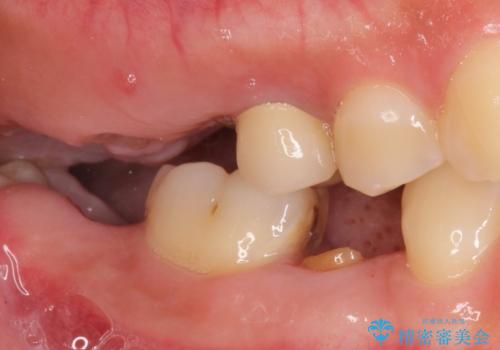

- う蝕により奥歯がボロボロで咬めないことを主訴に来院された患者様です。

奥歯2本(右上76)はう蝕が深く保存不可能な状態であったため、やむなく抜歯しました。

インプラントも入れ歯も抵抗があるとのご相談により、自家歯牙移植を提案しました。

使っていない親知らず(右上8)を右上7抜歯窩に移植し、支台歯としてブリッジによる補綴治療を行いました。